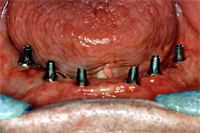

Eineinhalb Monate später sind die Implantate perfekt eingeheilt. Abb. 3 zeigt das klinische Bild der eingeheilten Implantate mit entzündungsfreien Schleimhautverhältnissen. Dazwischen sieht man die drei Druckknopfimplantate als provisorische Versorgung; sie geben der Prothese guten Halt während der Behandlungszeit.

In diesem Stadium wird nun der Abdruck mit ganz speziellen Übertragungsteilen (Abb. 4) für den Techniker genommen. Das alles verläuft für den Patienten völlig schmerzlos.